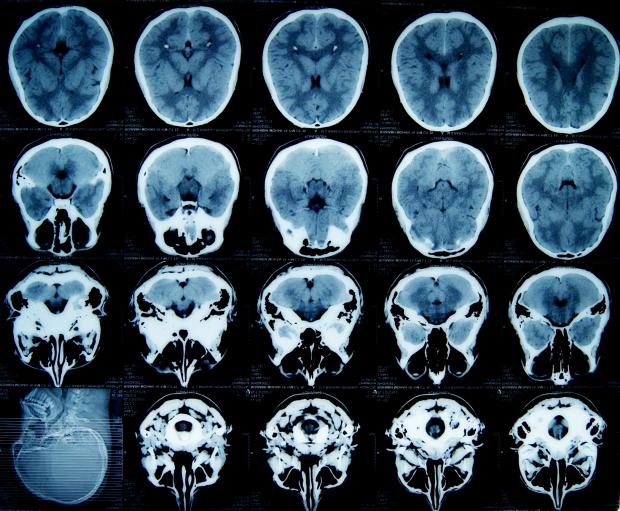

Towards a Clearer Picture in Biomedical Imaging: An Improved Algorithm for Photo Acoustic Tomography

In a collaborative study between the Indian Institute of Science (IISc), Bangalore, and the University of Twente, The Netherlands, researchers have designed a new algorithm for image recovery in Photoacoustic Tomography (PAT). PAT is an important non-invasive biomedical imaging technique where the optical contrast rendered by laser beams and the superior resolution of ultrasound waves are used to study biological tissues. The new algorithm works better with higher accuracy as compared to the conventional ones in use today.

Non-invasive imaging is important in biological research and in the diagnosis and treatment of various diseases. In imaging using PAT, a laser light is first shone on the target tissue. Oxygenated haemoglobin, non-oxygenated haemoglobin, water and lipids are the major light absorbing agents (chromophores) in living tissue. As light energy is absorbed, the target tissue undergoes a temporary elastic expansion. This leads to the emission of acoustic waves due to a phenomenon called the ‘photoacoustic effect’. The emitted ultrasonic waves are then detected by ultrasonic transducers placed outside the tissue and are further processed to generate a complete image. This technique provides high-resolution structural, functional, and molecular imaging of organelles, cells, tissues, and organs. It also provides details on the physiological properties, such as the blood haemoglobin concentration and oxygen saturation.

Image reconstructions, in techniques such as PAT, rely on the powerful algorithms that work in the background to conjure up the image from the measured data –the acoustic waves in this scenario. Since the equation governing photoacoustic wave propagation and the relation connecting the initial acoustic profile to the optical absorption distribution are both known, a reconstruction algorithm should aim to directly estimate this absorption map using the measured acoustic signals. Nevertheless, most of the existing algorithms either recover only the initial acoustic profile or rely on the reconstructed acoustic profile to subsequently estimate the optical absorption map in a second step. This two-step approach can result only in qualitative images due to the undesirable dependence of the initial acoustic profile on the optical source positions.

The researchers have now designed a one step approach to solve these challenges. “Most of the work in PAT is focused on developing better instruments for imaging and there is less stress on the development of better algorithms”, points out Ms. Mamatha Venugopal, a research scholar from IISc who is a member of the study group. Though one-step recovery of the optical absorption map is believed to be advantageous, such algorithms have not been attempted due to their hectic computational load. Ms. Venugopal and her team have tackled this problem by proposing a 'stochastic search' algorithm for the one step recovery of the optical absorption map from the measured acoustic signals. This method not only delivers quantitative images with an improved accuracy, but also side steps the feared computational load.

For the reconstruction, the area to be imaged is first broken up into a grid and each of the boxes is assigned a variable as its absorption parameter. A vector is constructed with these variables as its components, which defines the overall absorption profile. In the newly developed algorithm, this absorption vector is modelled as a stochastic process evolving with time. In the first step of the algorithm, the absorption profile vector is assigned a random distribution, say one in which all grids have zero absorption.  The acoustic wave profile can be calculated by solving the photoacoustic equations with the absorption profile as the input. In the subsequent steps, the absorption profile vector is iteratively modified such that, with every iteration, the misfit between the measured and calculated acoustic profiles approaches zero. The researchers found that the quantitative accuracy of the recovered absorption map using the new algorithm from both numerical and experimental data is good with an overall error of less than 10%.